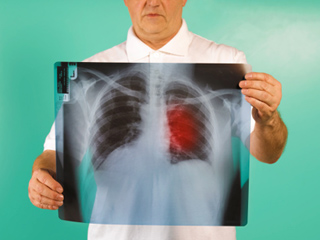

फेफड़ों का कैंसर (Lung Cancer) दुनिया भर में पुरुषों में होने वाला सबसे आम कैंसर था, 2018 में डाइग्‍नोज किए गए नए मामलों की कुल संख्या का 15.5% योगदान करते हैं। मुख्‍य रूप से तीन- फेफड़े, प्रोस्टेट और कोलोरेक्टल कैंसर, सभी कैंसर का 44.4% योगदान करते हैं (गैर-मेलेनोमा त्वचा कैंसर को छोड़कर)। इन आंकड़ों में 5% से अधिक योगदान देने वाले अन्य सामान्य कैंसर पेट और लिवर थे।

• फेफड़े का कैंस (20.9 लाख मामले)

• फेफड़े का कैंसर (17.6 लाख मौतें)